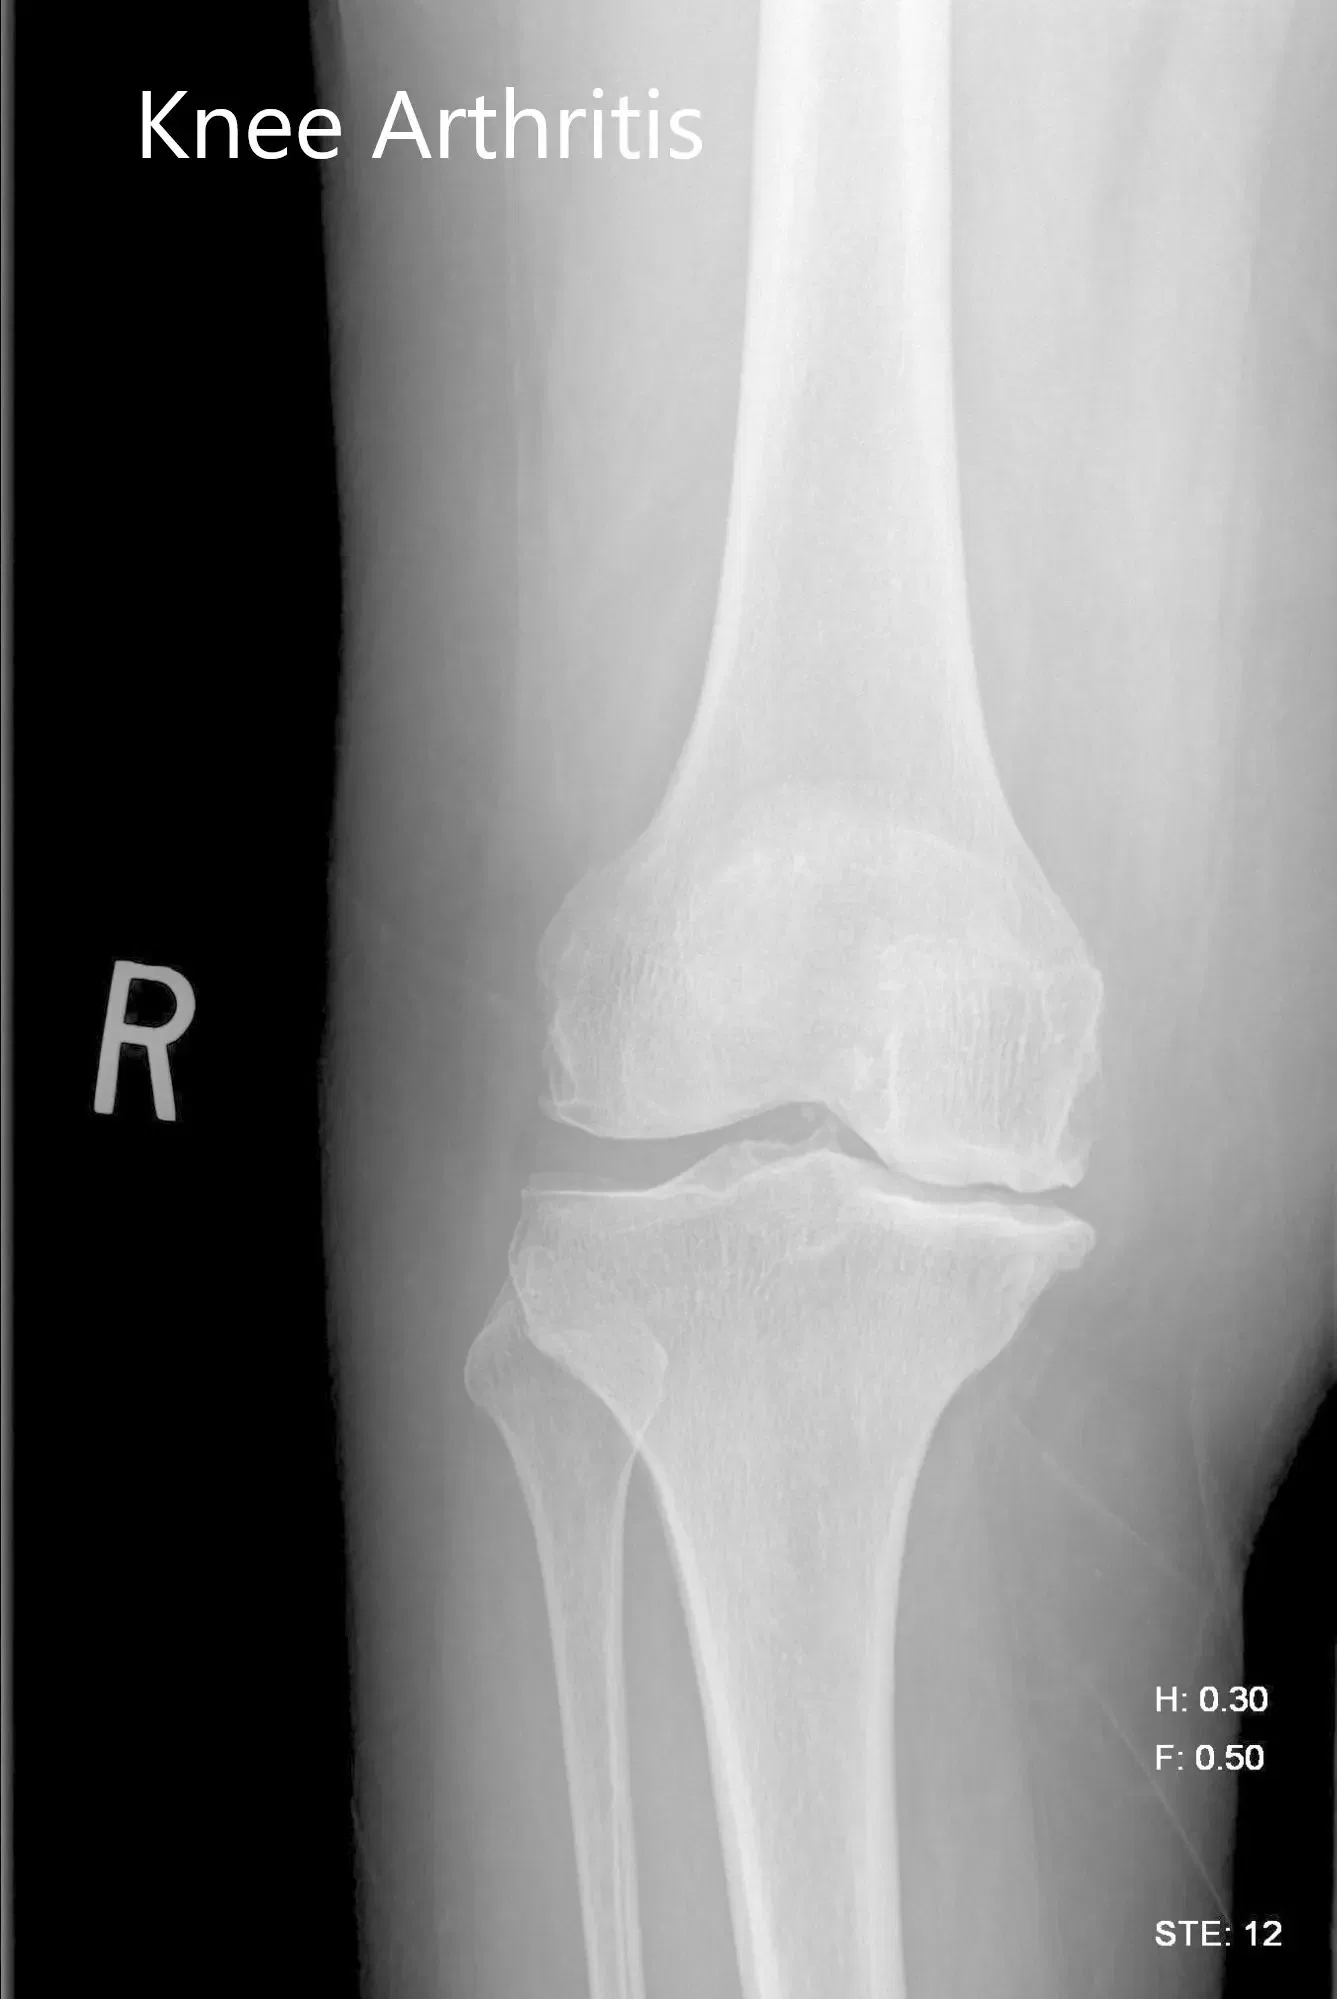

Se realizaron estudios de imagen que revelaron osteoartritis tricompartimental de la rodilla derecha con afectación severa del compartimento medial. Teniendo en cuenta la condición y las necesidades del paciente, se consideró candidato para un reemplazo total de rodilla con implantes personalizados. Otras opciones de tratamiento, incluidos métodos no quirúrgicos, se discutieron en detalle con él. Aceptó hacerse una prótesis personalizada de rodilla derecha.

Imagen de rayos X preoperatorios de la rodilla derecha mostrando vistas AP y laterales